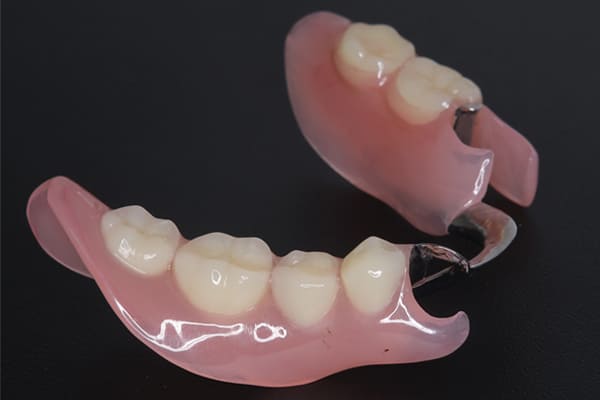

症例レポート[CASE.01]

義歯が合わず痛い、

見た目も気になる

- 性別・年齢

- 女性(40代)

- 主訴

- 下の義歯が合わず入れると痛みがある、見た目も気になるので外にはつけていかない

- 治療

- 下顎精密金属床部分入れ歯

- 治療期間

- 約2か月間

- 費用

- 55万円(税込)

入れ歯が沈み込むことを防止するストッパーがない入れ歯を装着されていたため、お食事により入れ歯が沈み込みお痛みがでている状態でした。

笑った際に、太いバネが左右に見えるため、あまり大きく笑うことを避けていらっしゃいました。

作製した入れ歯は、お食事の際に入れ歯の沈み込みを予防するため、適切なストッパーを付与することで、入れ歯は沈み込まなくなり、お痛みは消失しました。

右下のバネの位置は後ろに、左下のバネは見えづらい形態のバネを用いる設計とすることで笑った際にバネが見えないようになり、気にされることはなくなられました。

裏側の見えない部分は金属を用いることで、お食事の際の入れ歯の動き、沈み込みを抑えお痛みがでづらく、入れ歯の動きが抑制されることで、長期的に残りの歯に負担のかかりにくい設計としました。